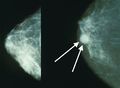

تصوير الثدي يظهر ثدياً طبيعياً (اليسار) وثدياً مصاب بالسرطان (اليمين).